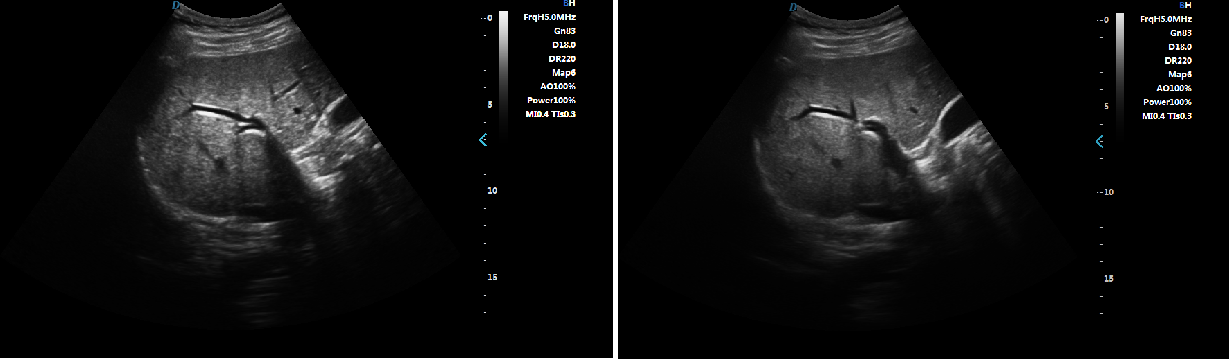

Trapezoid Imaging

Trapezoid imaging is a kind of expanded imaging, which is transformed into a trapezoid on the basis of the original rectangle, and

the left and right sides are expanded to a certain extent, achieving a wider field of view. The principle of ultrasound imaging is

to scan the human body with ultrasonic sound beams, and obtain images of internal organs by receiving and processing the reflected

signals.